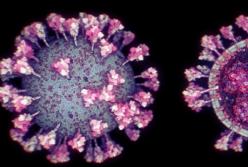

Ученые создали самую точную 3D-модель коронавируса (видео)

Ученые создали самую точную 3D-модель коронавируса (видео)

3D-модель коронавирусаРазработка демонстрирует современную структуру вируса SARS-CoV-2 на уровне атомов и выявляет детали, которые ранее было невозможно увидеть, передает FaceNews.